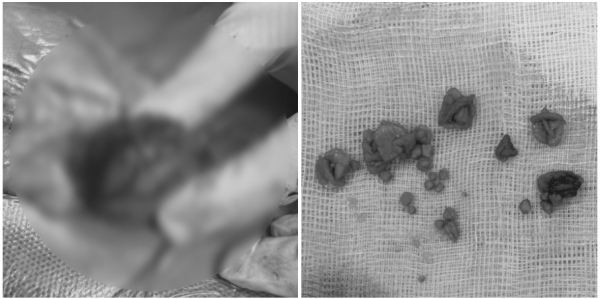

[방광결석 제거 수술]

방광결석 제거 수술을 진행했습니다.

수술은 안전하게 마무리되었으며,

제거한 결석은 성분 분석을 위해

외부 기관으로 의뢰했습니다.

: 칼슘옥살레이트 80%, 스트루바이트 20%